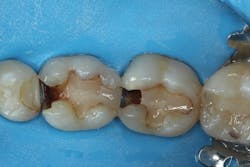

A patient presented with two failing composite restorations on teeth Nos. 30 and 31 (figure 1). A DermaDam rubber dam (Ultradent Products) was placed. This rubber dam was used because it has adequate thickness to displace tissue, yet sufficient compliance to stretch over larger clamped teeth without tearing. Rubber dam placement is used for only about 12% of operative dentistry procedures.1 Placing a rubber dam not only prevents salivary contamination of adhesive bonding procedures, but it also filters discarded dental materials, displaces the tongue and cheek, and reduces dental mirror condensation. The additional time required to place the rubber dam can be easily compensated for by these time-saving advantages, particularly when working on multiple restorations.

Figure 1: Initial presentation of failing composites on teeth Nos. 30 and 31